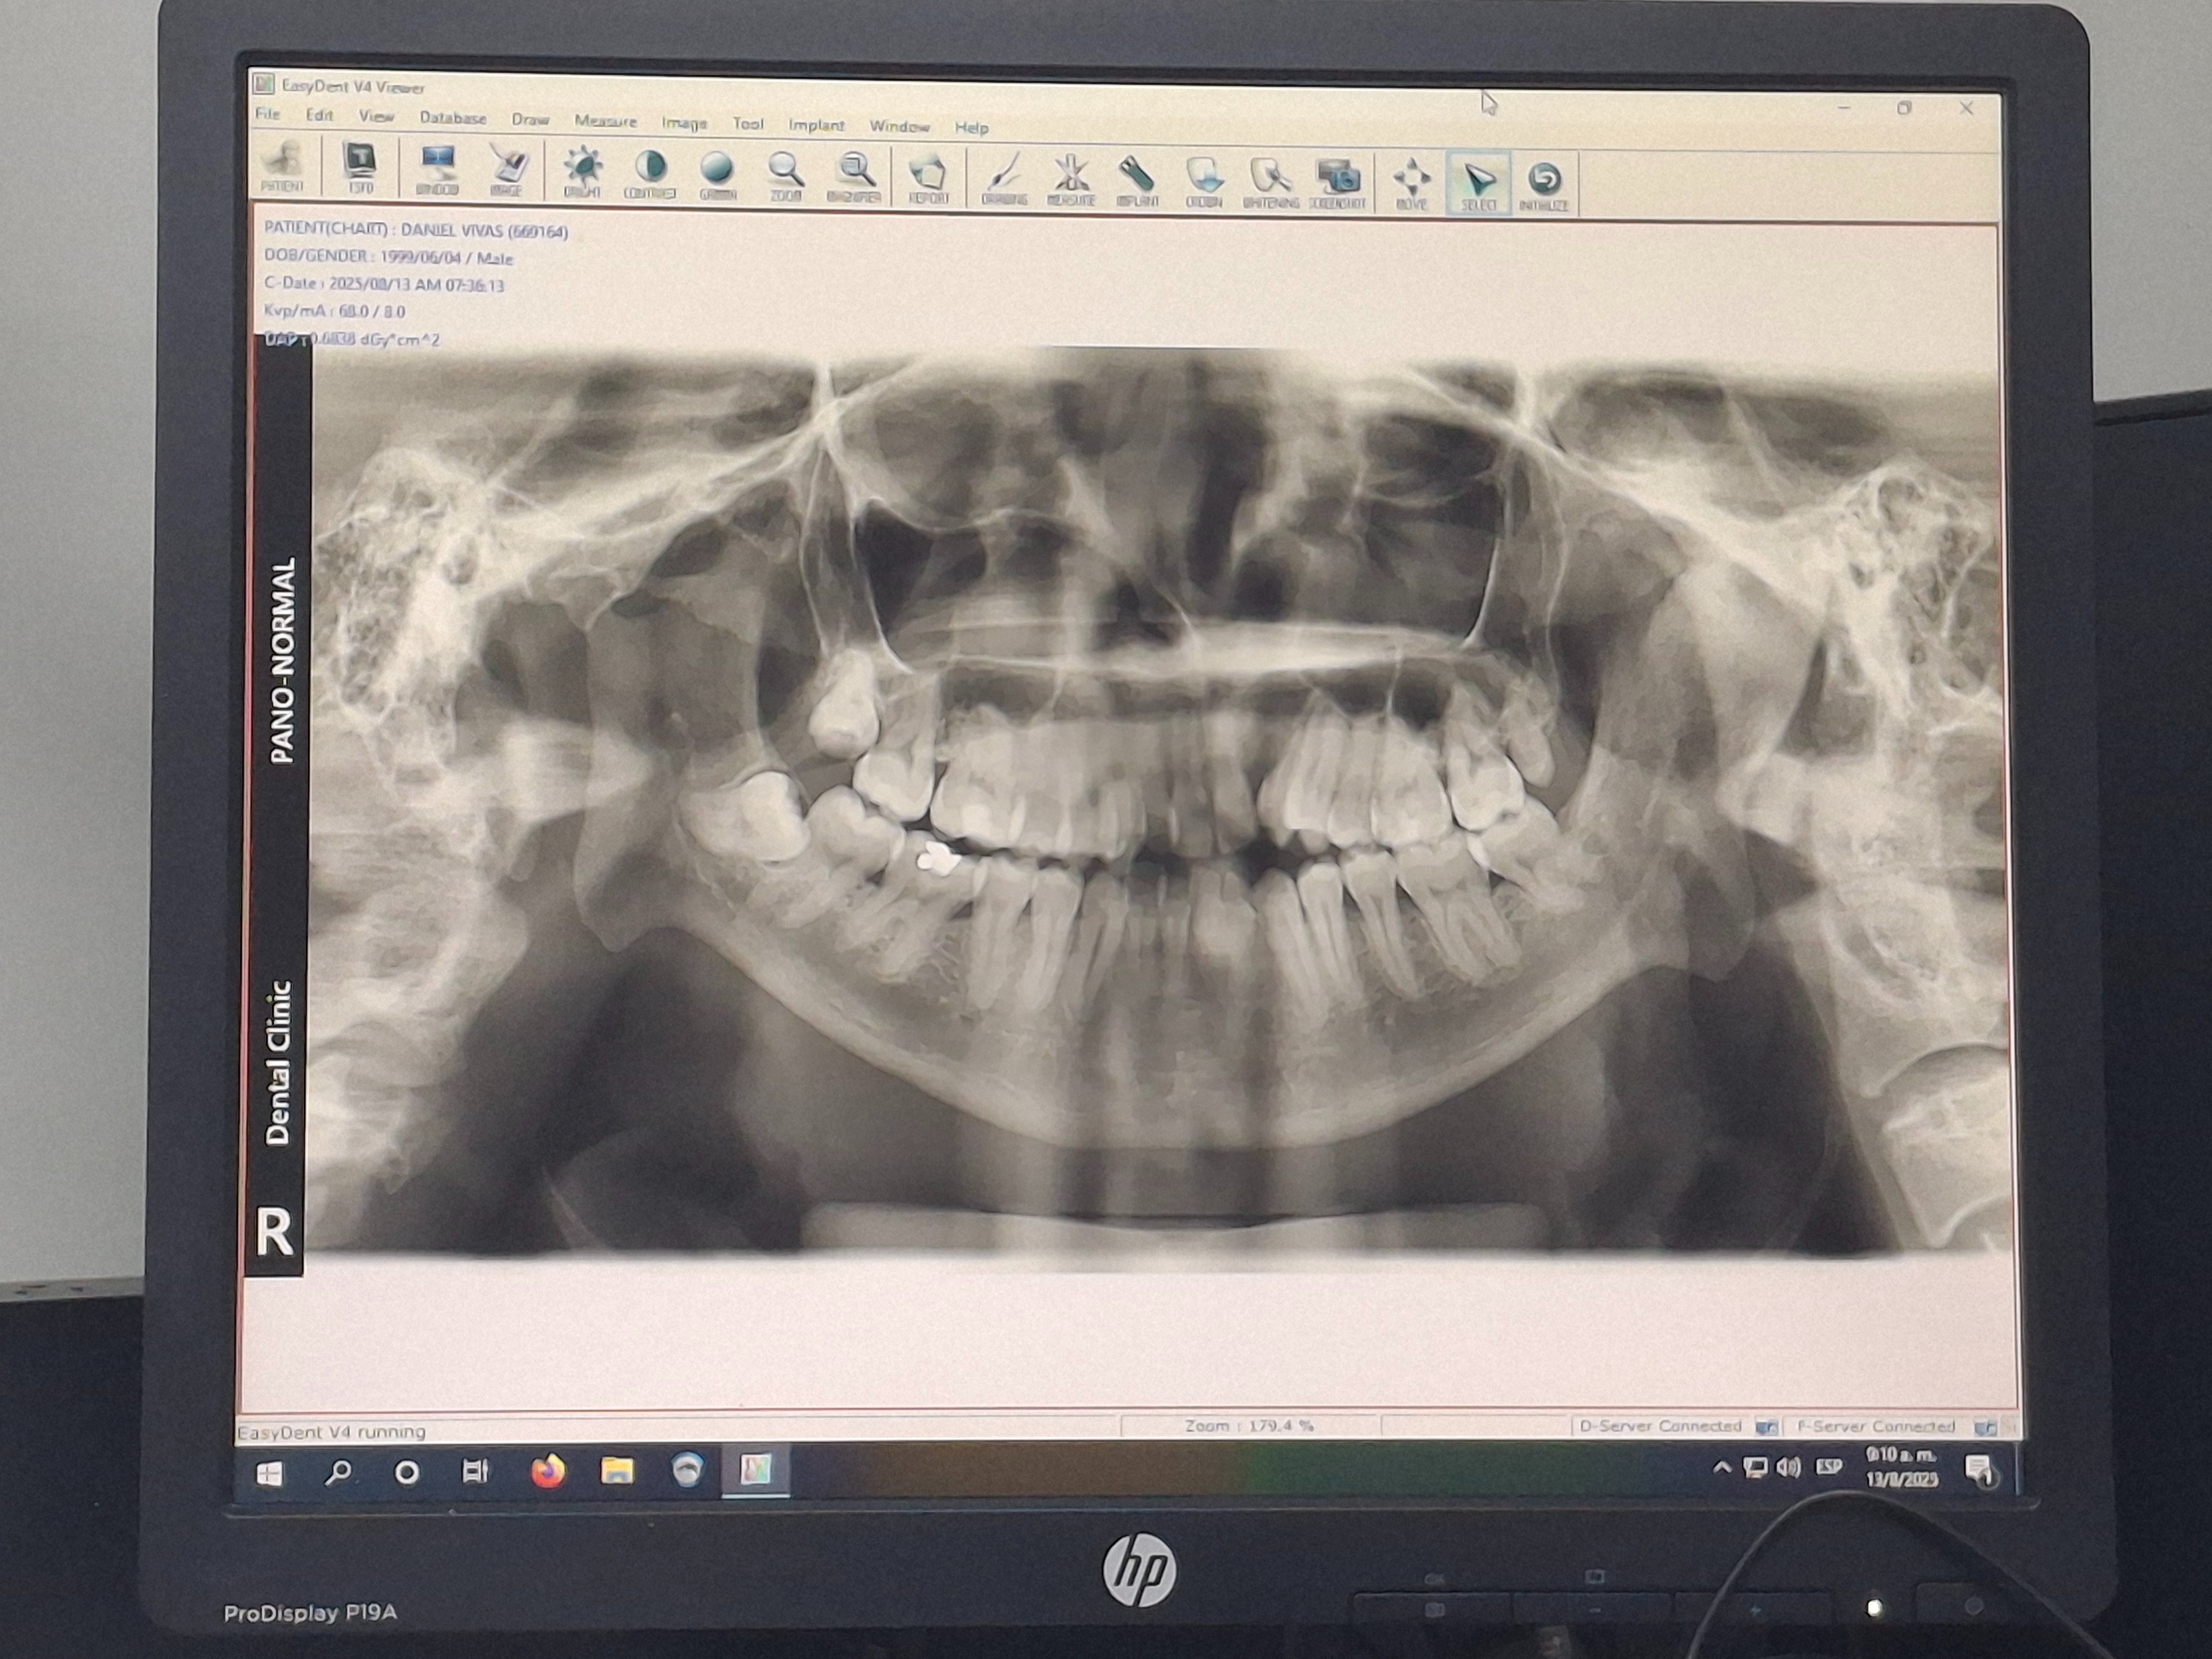

En 2020, se confirmó la implacable verdad: los huesos estaban fusionados. Padecía una anquilosis mandibular total. Me sometí a una cirugía compleja donde cortaron la fusión e implantaron músculo para evitar el contacto. ¡Pareció un éxito! Pero mi alegría fue fugaz. Los huesos, con una tenacidad espeluznante, se volvieron a unir, creando una densa "bola de hueso" en mi lado izquierdo.

Hoy, mi apertura bucal es de apenas 1 milímetro. Llevo años condenado a comer solo líquidos, puré y cosas que sean muy blandas, cuando lo ideal y normal en todo ser humano, es el disfrute del simple y glorioso placer de un bocado crujiente. Es una tortura psicológica. Ver a otros comer me inflige una frustración profunda, y las miradas inquisitivas de la gente en público han alimentado noches enteras de depresión y soledad. Solo anhelo la dignidad de comer una comida normal.

Los médicos han sido claros: necesito urgentemente una prótesis de ATM para que los huesos nunca vuelvan a tocarse. Es la única forma de recuperar mi capacidad de masticar, de sonreír sin restricciones y, poder comer como una persona común y corriente.

In 2020, the relentless truth was confirmed: the bones were fused. I was suffering from total mandibular ankylosis. I underwent a complex surgery where they cut the fusion and implanted muscle to prevent contact. It seemed like a success! But my joy was short-lived. The bones, with terrifying tenacity, fused together again, creating a dense "ball of bone" on my left side.

Today, my mouth opening is barely 1 millimeter. For years, I have been condemned to eat only liquids, purées, and very soft things, when the ideal and normal thing for any human being is the enjoyment of the simple and glorious pleasure of a crunchy bite. It is psychological torture. Watching others eat inflicts a deep frustration upon me, and the inquisitive stares from people in public have fueled entire nights of depression and loneliness. I only long for the dignity of eating a normal meal.

The doctors have been clear: I urgently need a TMJ prosthesis so that the bones never touch again. It is the only way to recover my ability to chew, to smile without restriction, and to eat like an ordinary person.